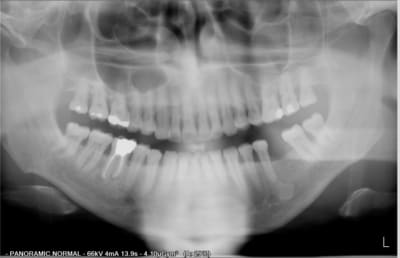

bonjours chers eugenoliens quelqu'un aurait aurait il une idée sur la condebsation en regard de l'apex de la 35 chez mon patient.dent vivante asymptomatique.quesaco??merci d'avance.

C'est probablement un cémentome.

d'apres la parodontite chronique de ce patient fumeur de 43 ans n'est elle pas a traiter.seul probleme pas de signe clinique tres peu de poches.le ttt ideal ne consisterait il pas en larret du tabac?quelles sont vos experiences face a de tels cas.merci.